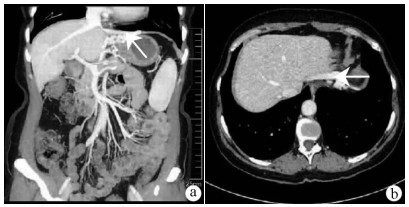

Research advances in hepatic echinococcosis with cavernous transformation of the portal vein

Maolin WANG, Yingmei SHAO

2021, 37(4): 965-968. DOI: 10.3969/j.issn.1001-5256.2021.04.053

Abstract(1082) HTML (420) PDF (1899KB)(57)

Abstract:

Compression by hepatic hydatid lesions may invade the portal vein and cause cavernous transformation of the portal vein (CTPV), which has difficulties and high risks in surgery, and conventional hepatectomy cannot achieve radical treatment. This article reviews the etiology, classification, clinical manifestations, and auxiliary examinations of hepatic echinococcosis with CTPV and summarizes the treatment strategies for this disease. It is believed that the treatment of hepatic echinococcosis with CTPV should combine the resection of hydatid lesions with the effective relief of portal hypertension, and revascularization and ex-vivo liver resection with auto-transplantation play an important role in radical resection.